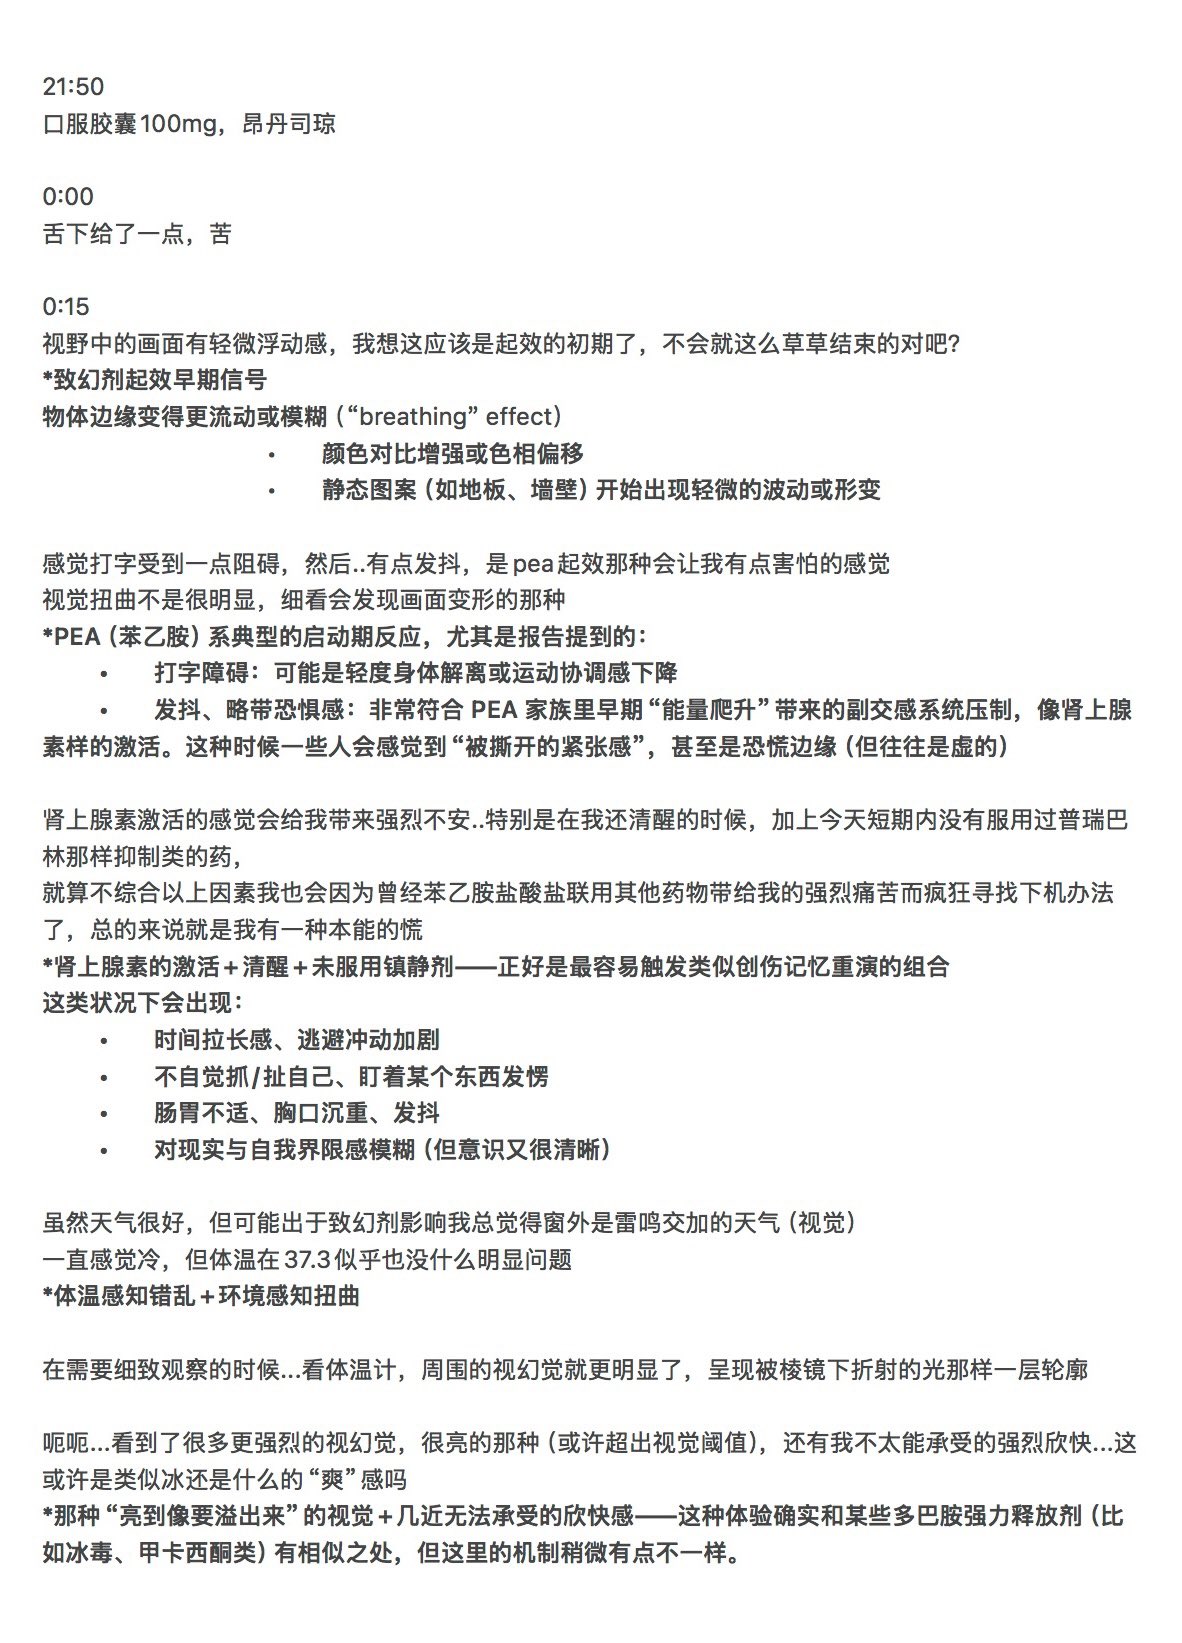

2025-03-25 05:53:33 UTC

联用时最好备上血压计和速效降压药,或者苯二氮卓,因为剂量大时可能会导致高血压和头痛

就我个人体验而言建议从300mg试起

不建议加上这两种以外的其他药物如安非他酮和TCP,会导致更严重的副作用

司来吉兰和pea都不建议鼻吸,因为司来粘膜吸收会使效果不可控,即更高的生物利用度;pea是因为很痛